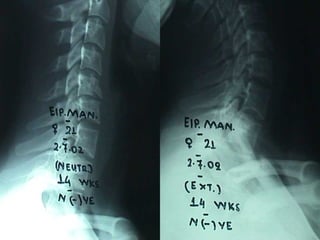

RRaaddiioollooggiiccaall

eevvaalluuaattiioonn

RRaaddiioollooggiiccaall ppaarraammeetteerrss

 KKyypphhoossiiss ooff tthhee

vveerrtteebbrraall bbooddyy

 SSeeggmmeennttaall

kkyypphhoossiiss

 DDiisscc hheeiigghhtt

 VVeerrtteebbrraall bbooddyy

hheeiigghhtt::BBeecckk iinnddeexx